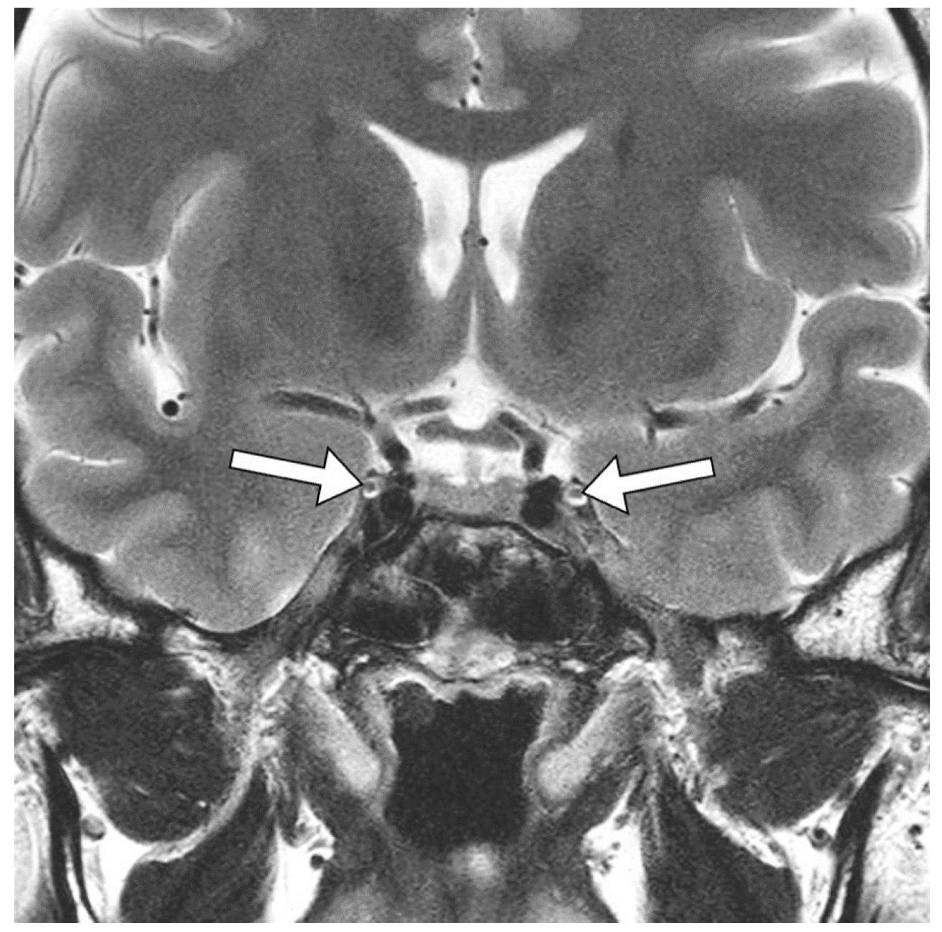

問題 32 頭部T2強調冠状断像を示す。矢印が示す解剖構造はどれか。

1. 視神経

2. 動眼神経

3. 滑車神経

4. 三叉神経

5. 外転神経